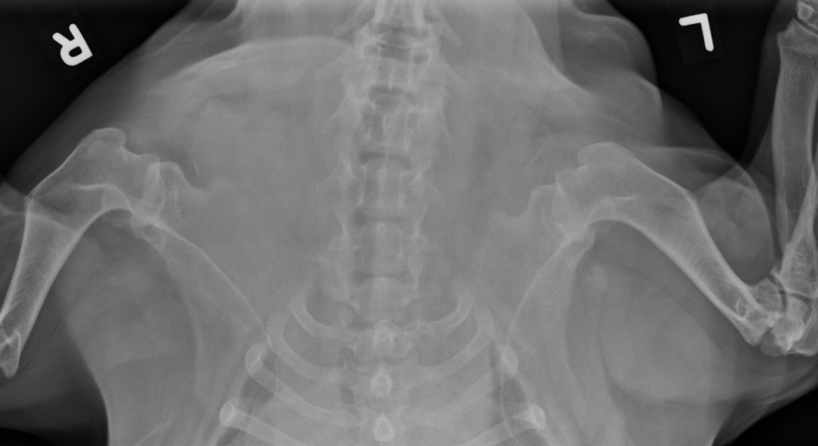

Q

8 months old female German Shepherd

Painful elbows

A

Both elbows: the anconeal process is ununited, the margins of the anconeal process and olecranon are markedly irregular and periosteal proliferation is present.

Marked intramedullary sclerosis of the olecranon and subtrochlear region of the proximal ulna is visible.

Diagnosis: Ununited anconeal process (UAP) and panosteitis of the ulnas.